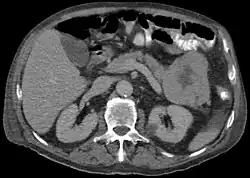

Acinar cell carcinoma of the pancreas

Acinar cell carcinoma of the pancreas, also acinar cell carcinoma, is a rare malignant exocrine tumour of the pancreas. It represents 5% of all exocrine tumours of the pancreas, making it the second most common type of pancreatic cancer.[1] It is abbreviated ACC. It typically has a guarded prognosis.

ACC are typically large, up to 10 cm, and soft compared to pancreatic adenocarcinoma, lacking its dense stroma. They can arise in any part of the pancreas.[2]